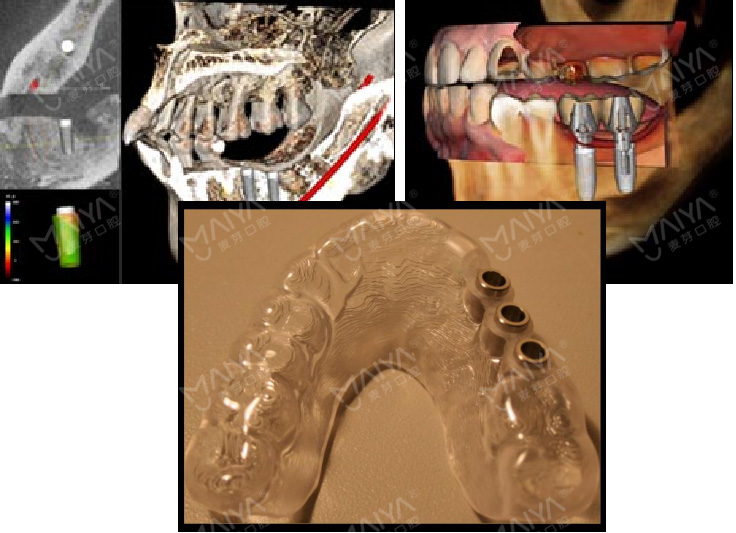

对于缺牙较多、多年缺牙未修复或牙槽骨吸收严重的人来讲,传统"盲种"一旦医生判断失误,就会导致种植体植入位置、角度不精确,造成日后种植牙受力不均、松动等情况,甚至直接导致种植失败。为规避"盲种"风险,"麦芽MAC数字化精确种植牙"应用口腔领域的数字化技术,通过CBCT、AI口扫取模、AI智能口腔体检等精确获取患者全口牙床位置,牙槽骨深度、厚度及角度等信息,并能直接在计算机上建成3D模型,全面向医生提供患者精确的颌面部影像数据。好比一幅带有导航仪的地图,医生能根据每名患者的口腔情况,精确制定个性化治疗方案,精确定位种植体理想位置。

此外,"麦芽MAC数字化精确种植牙"中的数字化分析模拟与方案设计、手术模拟导航技术等,能在计算机软件中预先设计种植方案,再通过3D可视化技术和3D打印技术制作种植导板,由此精确避开神经、血管位置,让种植牙牢牢地扎下根,彻底告别了传统"盲种"切开、翻开牙肉、缝合、拆线等步骤的弊端,同时大大缩短手术时间,患者身体负担更少,术后恢复更快。值得一提的是,MAC数字化精确种植牙还能对患者的牙颌面影像进行二次分析和处理,在计算机上精确呈现方案设计界面,模拟种植,让患者全程参与其中,并提前预知自己的种牙效果。